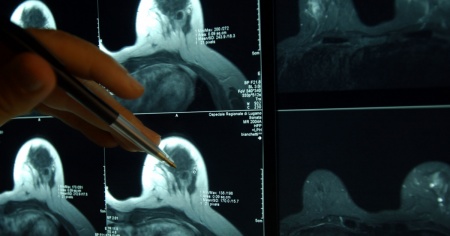

LUGANO - L'errore medico non c'è stato. È stata prosciolta la radiologa accusata di lesioni colpose gravi per non aver diagnosticato un tumore al seno a una paziente sottopostasi a un controllo nel 2019. Lo riferisce la Rsi.

La dottoressa, che all'epoca dei fatti lavorava alla Clinica Moncucco, aveva disposto una mammografia 2D e un'ecografia, ma non una mammografia 3D. Con i risultati degli esami a sua disposizione al momento, il suo non rendersi conto che vi fosse un tumore non può ritenersi in violazione dell'arte medica, ha detto il giudice Siro Quadri.

La paziente ha ricevuto la diagnosi soltanto un anno più tardi.